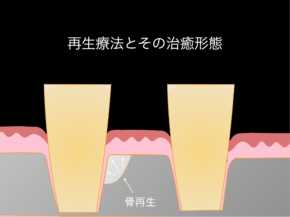

歯周組織再生療法(再生療法)とは?

しかしながら、歯周病治療の中で歯周外科手術と呼ばれる治療方法があり、

その中でも、歯周組織再生療法と呼ばれる失った骨を再生させる方法もございます。

下記に10年前に行った再生療法の症例をご紹介します。

失った骨の形態や噛み合わせなどにより、全ての患者様に再生療法が適応できる訳ではないですが、現在では症例や材料により保険適応ができる症例もございます。